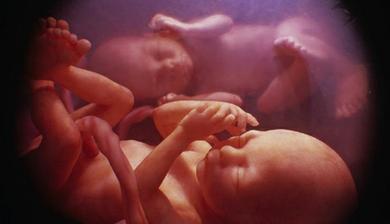

Jak asi víte, těhotenství je členěné na tři časové úseky, kterým říkáme trimestry – každý z nich trvá tři měsíce. Každý z trimestrů je zcela specifický, probíhají v něm určité charakteristické změny, podstupuje se vyšetření a nesou s sebou jiné pocity a obavy nastávající maminky.

- II. trimestr = 13. - 28. týden těhotenství

zázrak lidské života na videu